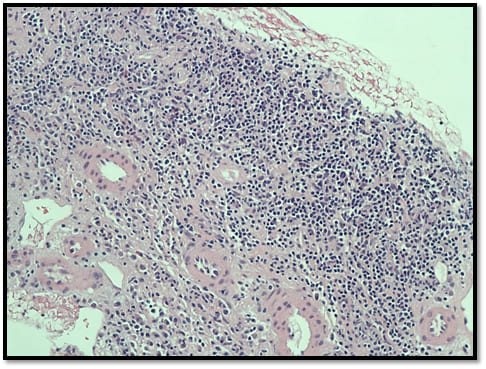

Computed Tomography scan of the abdomen and pelvis showed diffusely enlarged renal allograft measuring 15.6 cms x 9.8cms x 9.1cms without any hydronephrosis, calculi or masses. Doppler Ultrasound showed similar findings with perinephric collection, but no renal artery stenosis. Transplant biopsy showed acute cellular rejection of the renal allograft with interstitial infiltration with lymphocytes, plasma cells, and occasional eosinophils classified as Banff IB (Image 1).

Differential diagnoses for Leiomyoma in the graft were Leiomyosarcoma, angiomyolipoma, and renal cell carcinoma [4,5]. These were ruled out based on histologic findings. Leiomyoma in the presented case histologically consisted of whorls of cytologically bland spindle cells with abundant eosinophilic cytoplasm (Image 1). On high resolution microscopy, it revealed absence of cytologic atypia and mitotic figures (Image 2).

Image 1: Renal Allograft biopsy with lymphocyte, plasma cells and occasional eosinophil infiltration: Acute Rejection.